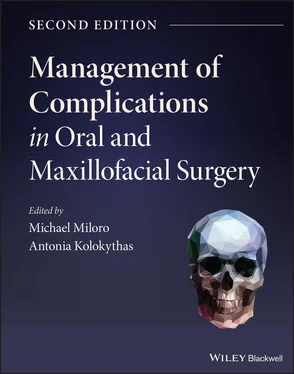

The phenomenon of peri‐implantitis is a well‐recognized and frustrating clinical problem for dental implant surgeons and patients. Part of this frustration lies in the fact that unlike periodontal disease, which is well defined and organized into categories, peri‐implantitis remains a rather ambiguous and debated term with variable clinical presentation. Some surgeons prefer the term “peri‐implantosis” since there are instances where there is bone loss surrounding an implant, but an absence of inflammation, so the term “peri‐implantitis” would not technically apply [35]. Most surgeons agree that for a diagnosis of peri‐implantitis to exist the presence of gingival recession and implant exposure and bone loss should be present. The distinguishing factor between peri‐implantitis and peri‐implant mucositis is that peri‐implantitis has bone loss around the implant ( Figure 3.16), while peri‐implant mucositis does not exhibit bone loss since the inflammation is confined to the mucosa ( Table 3.5). The bone loss in peri‐implantitis has been referred to as a “saucer‐shaped” bone defect around the implant on clinical examination and a peri‐implant radiolucency on radiographic imaging ( Figure 3.17). Peri‐implantitis often presents itself years after initial dental implant placement, and for this reason is included in the late‐stage infection category. Often, the peri‐implant bone loss is discovered incidentally on routine dental radiographs, and in the posterior region of the jaws, the presence of gingival inflammation, pain, BOP, purulence, and recession may go unrecognized by the patient for some time. Peri‐implantitis is believed to be due to biofilm formation on the implant surface with colonization by Staphylococcus aureus , which is an organism not typically seen with periodontitis. Risk factors include a history of periodontitis, smoking, poor oral hygiene, exposed implant threads, exposed surface coatings, and deep pocket depths. Treatment includes mechanical debridement with ultrasonic scalers or a titanium wire brush or the use of an erbium–YAG laser, implant surface decontamination with citric acid solution (5%), chlorhexidine irrigation, local antibiotics (25% tetracycline gel or fibers), systemic antibiotics (ornidazole or metronidazole), and improved oral hygiene that may be improved with an alteration in the prosthetic design (e.g., ridge‐lap prosthesis, or splinted prosthesis). Also, surgical reconstruction may include regenerative surgery with bone grafting, GBR, or connective tissue grafting, or resective surgery with osteoplasty and apically repositioned flaps. If there is retained cement in the area, it should be debrided. Of the options of debridement, resection, grafting, and GBR, bone grafting and GBR may have improved bone fill and pocket depth reduction in cases of peri‐implantitis.

A clear distinction needs to be made between increased probing depths around a dental implant and an established diagnosis of peri‐implantitis. Often bone levels around the implant may be ideal; however, a soft tissue pannus formation, in the form of a gingival pseudo‐pocket, may lead inexperienced clinicians to diagnosis a case of peri‐implantitis [36]. Although this excessive pseudo‐pocket is not ideal and can lead to oral hygiene issues with eventual bone loss, this is not an inevitable consequence. With meticulous oral hygiene maintenance and close follow‐up, this region can often be maintained without any untoward effects. In certain circumstances, gingivectomy may be required for excessive soft tissue, but careful attention must be paid to not affect the esthetic outcomes of the soft tissues, especially in the anterior esthetic zone. Once a diagnosis of peri‐implantitis has been established, the clinician must control the contributing factors, assess the presence of keratinized tissue, and evaluate the implant surface, implant location, restorative issues, and the presence of parafunctional habits [37]. Since these factors have been discussed previously, the discussion will focus on the surgical management of the implant with localized bone loss and inflammation with the understanding that other contributing factors have been addressed in order to optimize the outcome. Many of the initial stages of peri‐implantitis can be managed similar to periodontal disease. Nonsurgical peri‐implant debridement includes chemical and mechanical debridement. Chemical debridement with various topical agents such as chlorhexidine, citric acid, hydrogen peroxide, and tetracycline can be used. Mechanical debridement with implant scalers, titanium brushes, and lasers can be used. These techniques should be combined with patient education on the use of meticulous oral hygiene to help decrease peri‐implant soft tissue inflammation allowing for increased tissue adherence (soft tissue seal) around the implant fixture [38]. This increased tissue tone decreases bacterial migration along the implant surface and can prevent further infection and bone loss. More advanced cases of peri‐implantitis, with up to 50% bone loss, must be assessed regarding a guarded long‐term implant prognosis. If the implant is deemed salvageable, this will require open surgical debridement, bone grafting with guided tissue membrane regeneration, and temporary removal of the existing restoration [39]. Once appropriate bone and soft tissue healing has occurred, with evidence of adequate osseous regeneration around the implant, the implant may be uncovered and prosthetically restored. Peri‐implantitis that has progressed to greater than 50% bone loss, implant mobility, and recurring infections often necessitate implant removal and bone grafting with delayed implant replacement and restoration ( Algorithm 3.7).

Algorithm 3.7: Peri‐implantitis